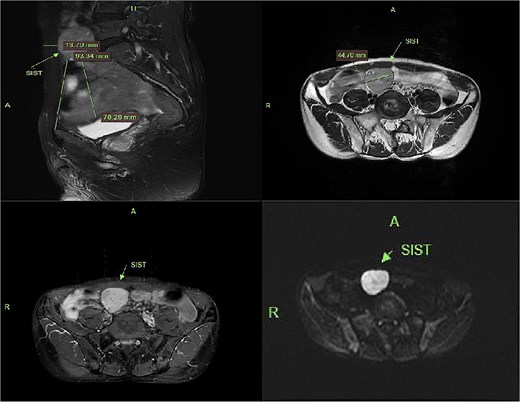

Contrast-enhanced CT demonstrated a well-circumscribed, round enhancing mass measuring 4 cm in diameter. Sagittal imaging showed the lesion positioned 0.9 cm from the bladder wall, 4.5 cm from the anterior abdominal wall, and 6.1 cm from the pubic symphysis (Fig. 2). The mass exhibited an intact capsule without evidence of rupture. MRI performed within a 24-hour period, sagittal imaging showed the lesion positioned 7.9 cm from the bladder wall, 1.3 cm from the anterior abdominal wall, and 9.3 cm from the pubic symphysis, and confirmed stable positioning and morphology, maintaining identical spatial relationships to adjacent structures (Fig. 3).

MRI demonstrates superior displacement of the tumor compared to CT, with isointense signal on T2-weighted fat-suppressed sequences, post-contrast enhancement, and hyperintensity on DWI at a b-value of 800 s/mm².